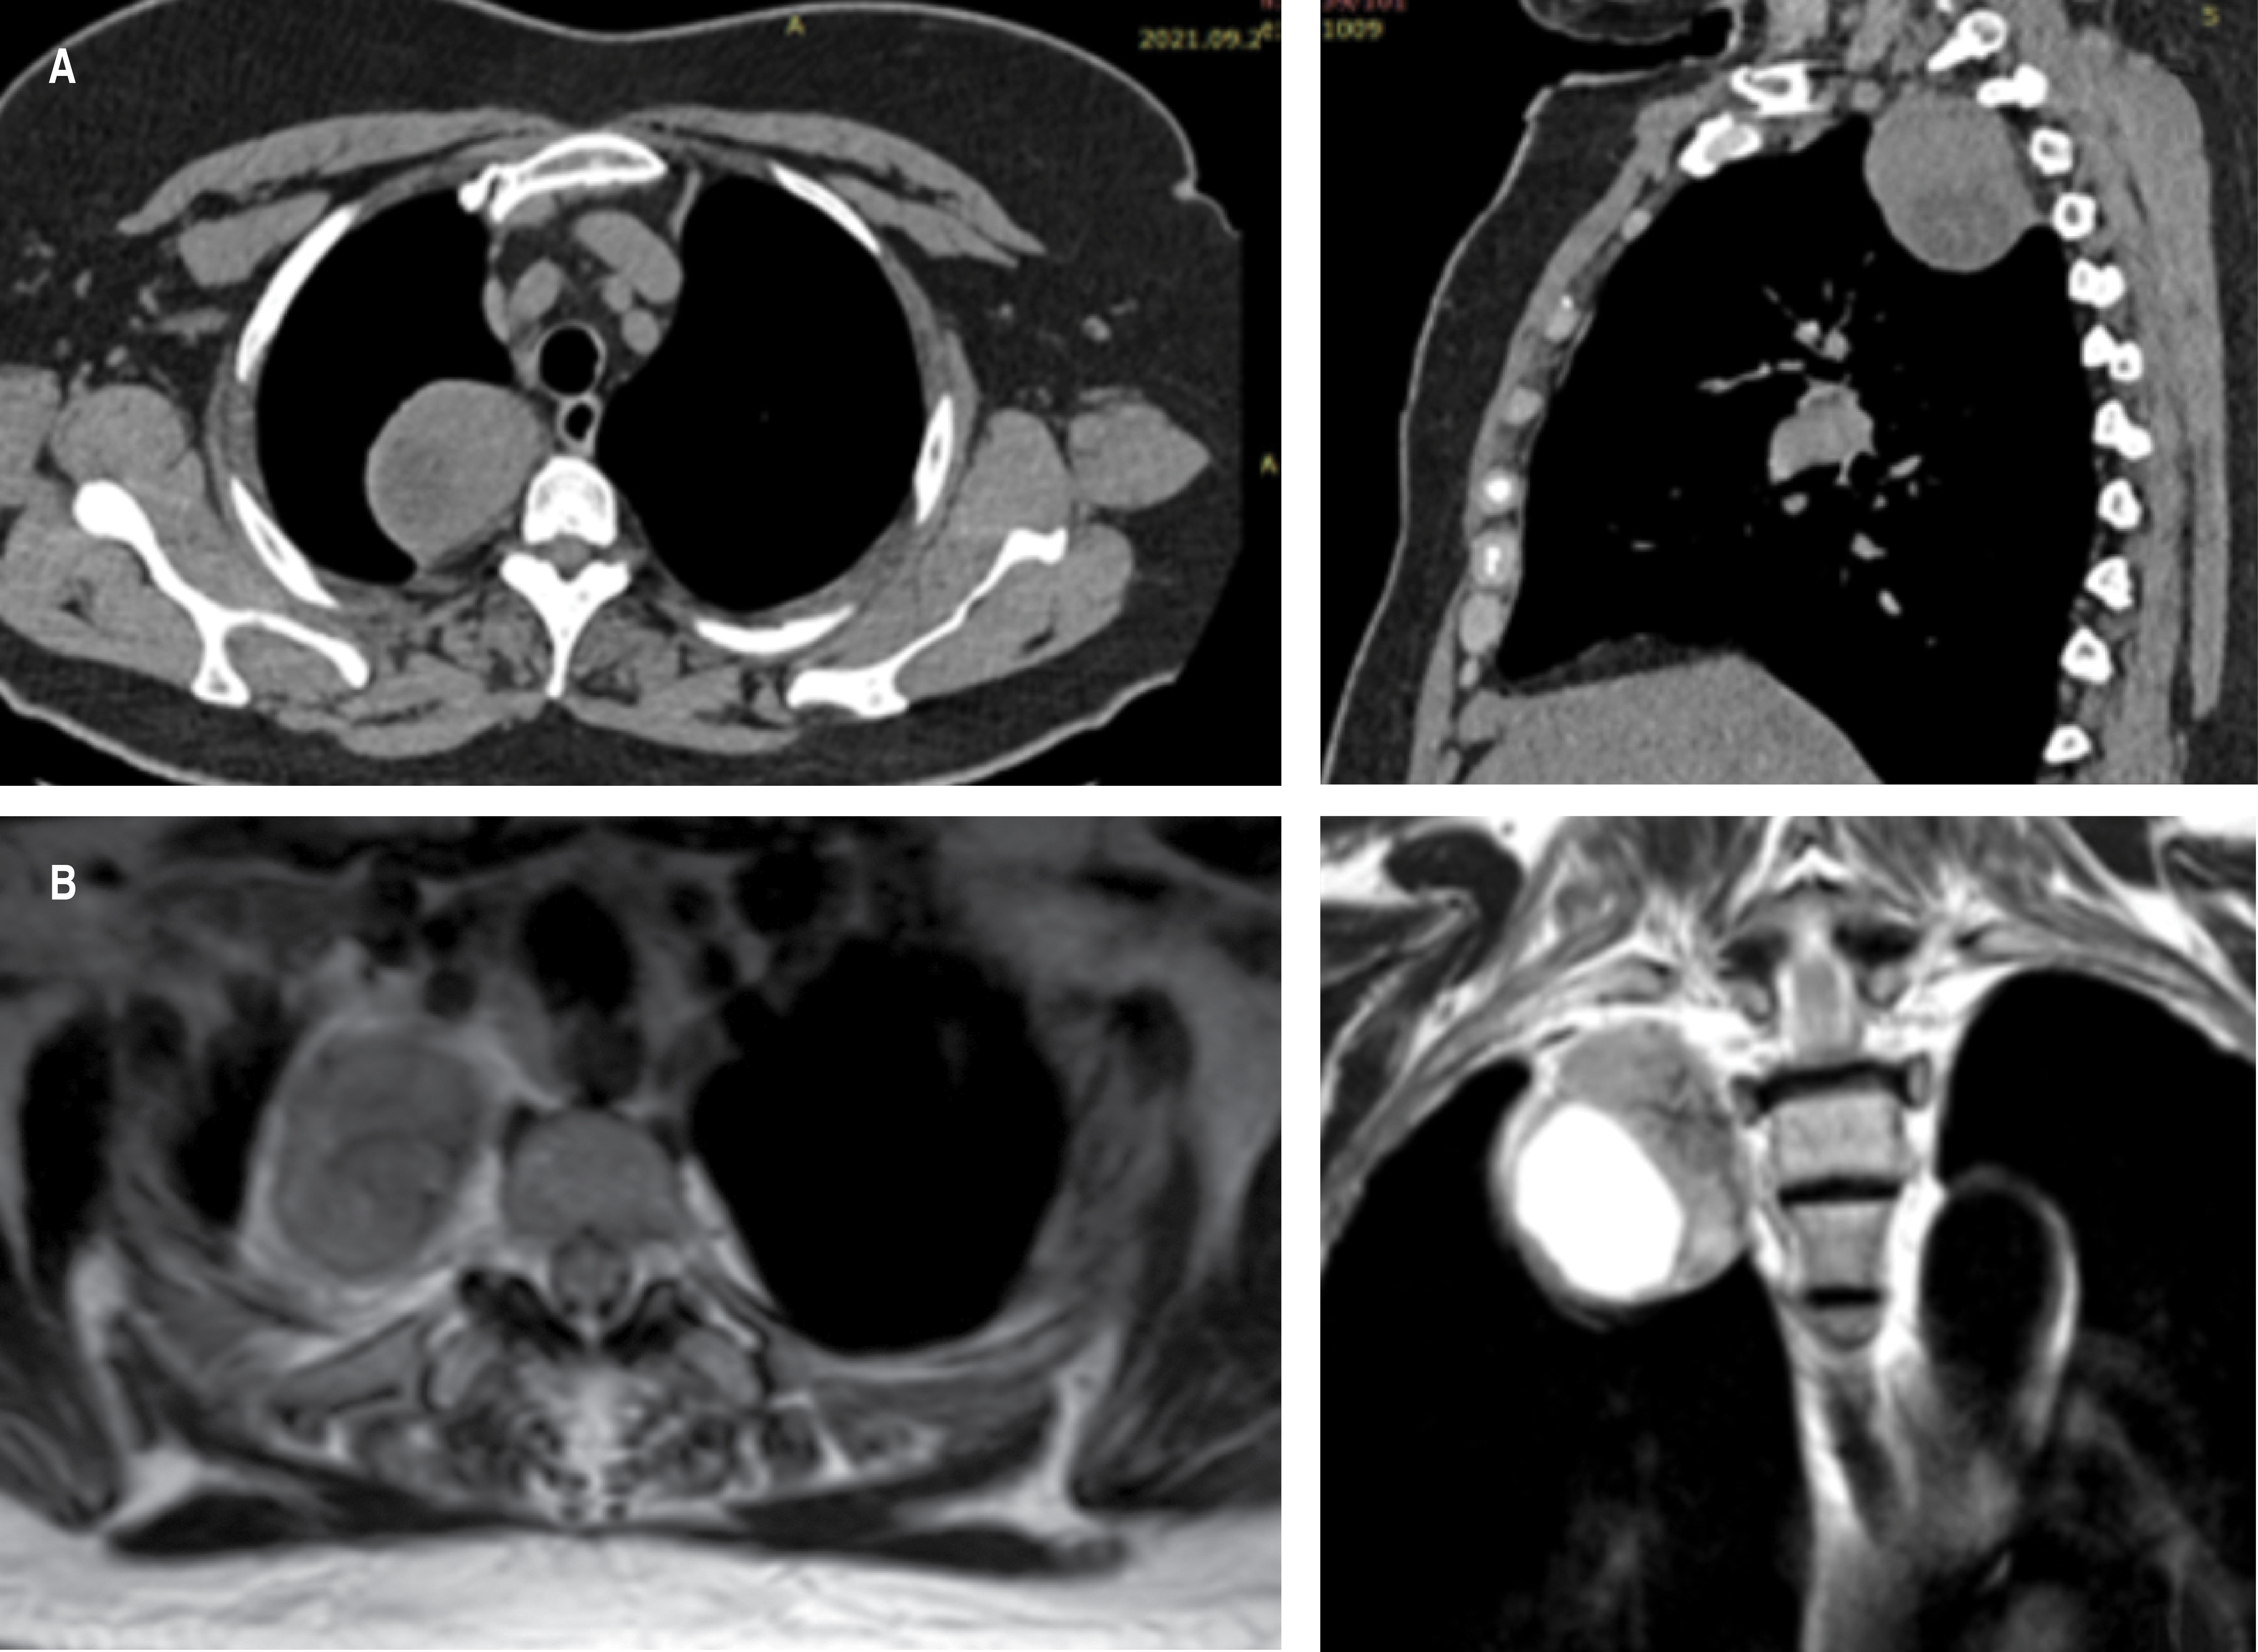

In imaging studies, peripheral sheath tumors are well-defined, hypodense tumors with low attenuation and contrast enhancement on computed tomography (CT). On magnetic resonance imaging (MRI) they are isointense on T1 and hyperintense on T2.1 MRI is the most sensitive method to define the presence and extent of the intraspinal component of the tumor. It is indicated when the tumor is contiguous to the neural foramen, when there is a widened intervertebral foramen, or when there is erosion of a vertebral body or pedicle.5

Female, 67 years old. Important antecedents: allergy to penicillin. Smoking denied. Her condition began after infection by SARS-CoV-2, where a simple chest CT scan was performed with incidental finding of posterior mediastinal tumor (Figure 1A). The study was completed with magnetic resonance imaging (Figure 1B) and the patient was sent to the Thoracic Surgery Service of the Instituto Nacional de Enfermedades Respiratorias Ismael Cosío Villegas, Mexico City. Preoperative examinations and tumor markers were normal. A two-port VATS approach was decided for tumor resection (Figure 2A), with findings of a nerve sheath-dependent tumor at the level of the second intercostal space, whitish, vascularized, 5 × 4 cm in diameter (Figure 2B), which was resected in its entirety without complications. Postoperative evolution was satisfactory, removing the drain on the third day, with adequate lung expansion. Pathology report of a peripheral nerve sheath tumor compatible with schwannoma, with immunohistochemistry positive for PS100 and enolase. Six-month follow-up with no evidence of tumor recurrence.